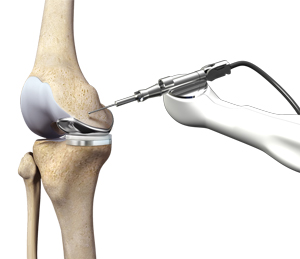

Minimally Invasive Knee Joint Replacement

Total knee replacement is a very successful surgical treatment for knee arthritis. Over the years, minimally invasive knee replacement surgical techniques have …

Continue reading “Minimally Invasive Knee Joint Replacement”